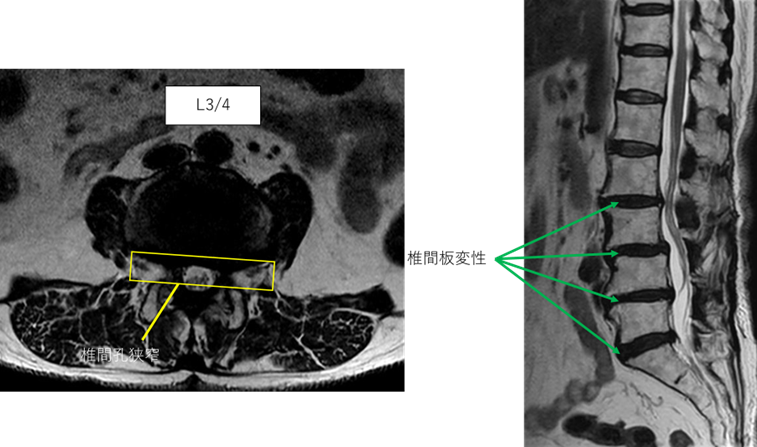

L1/2: 異常なし

L2/3: 椎間板変性症

L3/4: 椎間板変性症、両椎間孔狭窄

L4/5: 椎間板変性症

L5/S: 椎間板変性症

以上の事が画像上認められます。

L2/3、3/4、4/5、5/sに

椎間板変性症、椎間孔狭窄を認め、主症状の原因の可能性が高い。